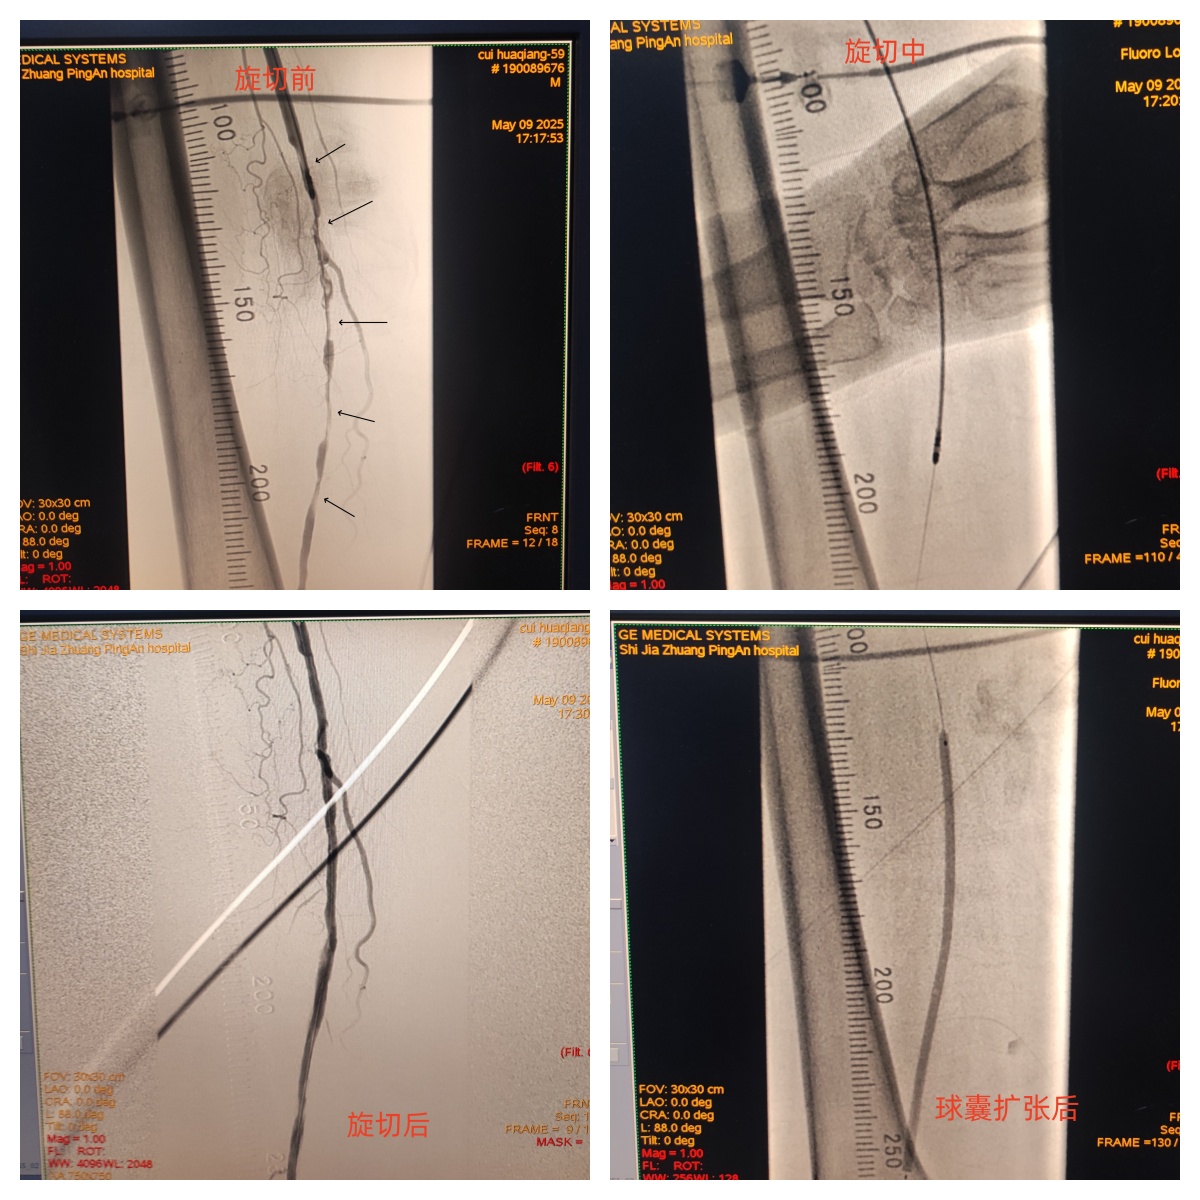

石家庄平安医院周围血管科率先引进先进的JETSTREAM血管斑块旋切系统,为下肢动脉硬化患者提供更优解决方案。该技术具有以下优势:

旋切+抽吸一体化:在切除斑块的同时主动抽吸碎屑,减少远端栓塞风险。

智能变径刀片:可适应不同血管直径(2.1-4.0mm),精准处理钙化、纤维化等复杂病变。

JETSTREAM血管斑块旋切系统,在局麻下即可进行,结合球囊扩张术,可快速改善患者下肢血流,让原本狭窄的血管恢复通畅,恢复行走能力,提升患者生活质量。